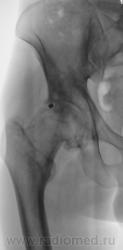

Почему-то на ум пришло сразу "Вот пуля пролетела ,и ага..".

это вероятно и есть состояние после огнестрельного ранения в виде ДОА 3 ст, инородное тело или нет?

Для точной локализации пули нужна попендикулярная ( как в "Двух капитанах" - палочки должны быть попендикулярны) проэкция. Может и не причина артроза?

КТ 2009 года.